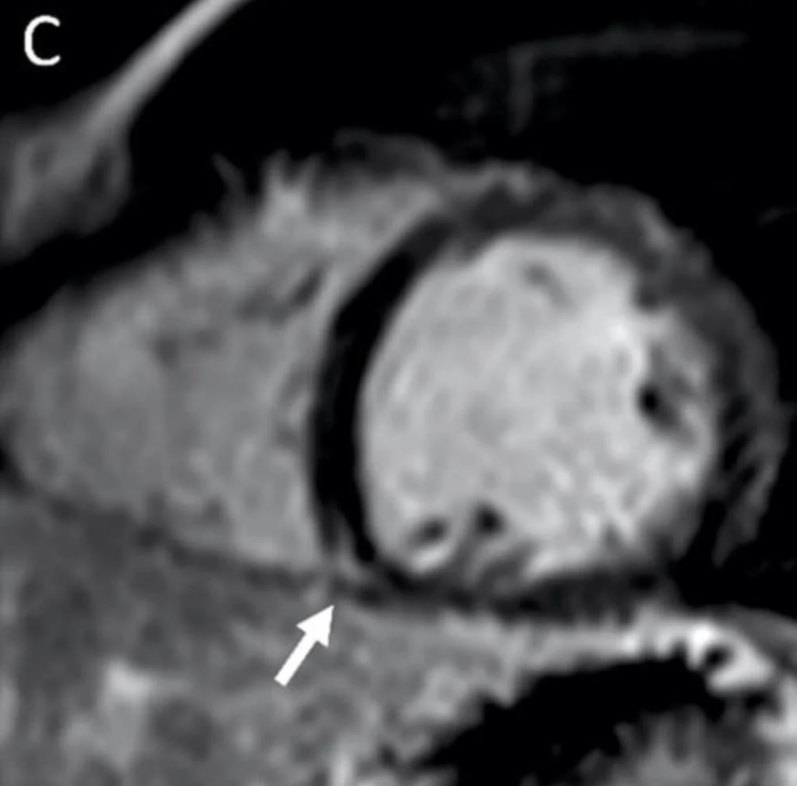

This photo gallery shows the variety of radiological presentations of COVID-19 (SARS-CoV-2) in medical imaging, including computed tomography (CT), radiograph X-rays, ultrasound, echocardiograms and magnetic resonance imaging (MRI). The radiology images show examples of typical COVID pneumonia in the lungs and the numerous complications the virus causes in the body in multiple organs, including the brain, kidneys, heart, abdomen and vascular system.

Ultrasound, especially hand-held ultrasound imaging devices, have become a primary imaging modality for novel coronavirus because of the ease to bag the device and sterilize it after use. CT and mobile X-ray systems are also used as front-line imaging systems for COVID-positive or suspected COVID patients.